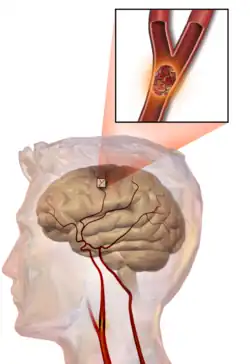

Illustration of an embolic stroke, showing a blockage lodged in a blood vessel

In thrombotic stroke, a thrombus[47] (blood clot) usually forms around atherosclerotic plaques. Since blockage of the artery is gradual, onset of symptomatic thrombotic stroke is slower than that of hemorrhagic stroke. A thrombus itself (even if it does not completely block the blood vessel) can lead to an embolic stroke (see below) if the thrombus breaks off and travels in the bloodstream, at which point it is called an embolus. Two types of thrombosis can cause stroke:

An embolic stroke refers to an arterial embolism (a blockage of an artery) by an embolus, a traveling particle or debris in the arterial bloodstream originating from elsewhere. An embolus is most frequently a thrombus, but it can also be a number of other substances including fat (e.g., from bone marrow in a broken bone), air, cancer cells or clumps of bacteria (usually from infectious endocarditis).[54]